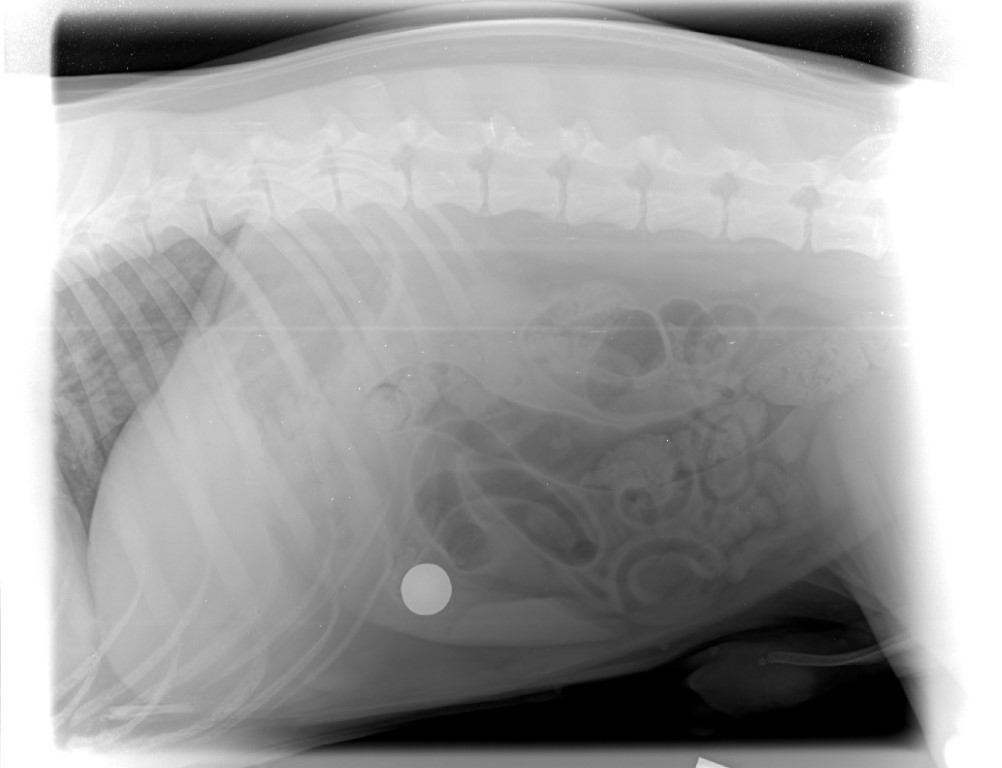

Xrays showed that he had swallowed a nice sized round fishing sinker (about 50 grams in weight).

Nearly $4,000 later he's back to his usual self.